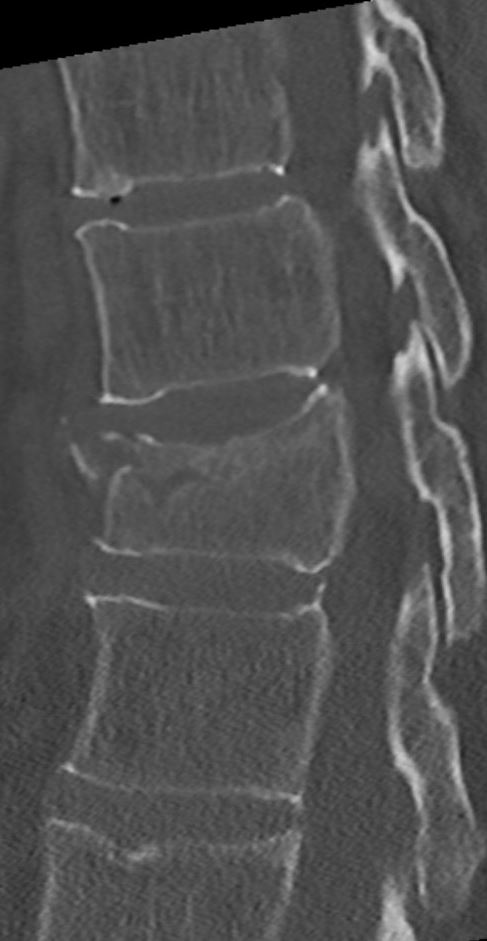

De breuk

Door een val of door een extreme buiging van de romp kan een breuk in 1 of meerdere rugwervels ontstaan. Afhankelijk van de plaats en het type breuk is de breuk stabiel of instabiel. Bij een stabiele breuk is alleen het wervellichaam gebroken en is het ruggenmerg niet in het gevaar. Bij een instabiele breuk is er wel kans dat het ruggenmerg beschadigd raakt of dat de breuk verder inzakt en daarmee de vorm van de wervelkolom verder verandert. Een stabiele breuk ontstaat meestal na een eenvoudige val, terwijl een instabiele breuk meestal na een val van hoogte of een verkeersongeval ontstaat. Om te bepalen of een breuk stabiel is, is er naast een Röntgen foto vaak een CT scan nodig. Ook wordt er vaak neurologisch onderzoek gedaan.

Afhankelijk van waar de breuk zich precies bevindt en of de breuk stabiel of instabiel is, zal uw behandeling bepaald worden. Stabiele breuken worden vaak met tijdelijke bedrust en later fysiotherapie behandeld, al dan niet in combinatie met een ondersteunend corset.